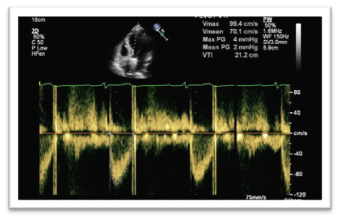

A complete 2D TTE study was performed in all subjects, using a Philips iE33 xMATRIX (USA) equipped with x5 transducer. All acquisitions were performed by same operator with subject in left lateral position. LVOT diameter measurements had an image recorded in 2D parasternal long-axis view with zoom mode activated. The gains were adjusted to optimize the blood tissue interface. The measure was made inner edge to inner edge, in mid-systole, parallel and adjacent to the aortic valve or at the site of velocity measurement. About LVOT VTI, the image was recorded with pulsed-wave Doppler in five-chamber view by placing the sample volume of PW Doppler at the base of the aortic leaflets. The proper time axis was bigger than 100 mm/s in order to obtain a better delineation, with low wall filter setting and adjustment of baseline and scale to maximize the size of velocity curve. VTI was traced.14,15 Apical two-chamber and four-chamber view were recorded for assessment of EF by Simpson’s biplane method. Matrix-array transducer was used for the acquisition of the 3DE data sets from four consecutive cardiac cycles during end expiration breath-hold in apical view (Figures 14).

Figure 4 Spectral pulsed wave Doppler of LVOT with manual tracing in apical five-chamber view.